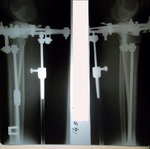

Основные крутки закончены, натаптываем ножки.

SAM_0460.JPG